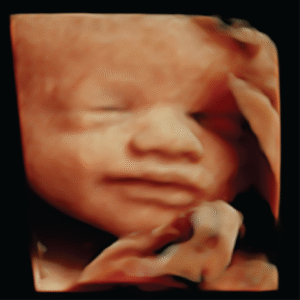

Explore our Photo Gallery and see the real results from Knit 4D Ultrasound. Every image you see  from 2D, 3D, 4D, to HD live ultrasounds  was captured by our highly trained team using our state-of-the-art ultrasound machine. We can begin creating amazing 3D/4D keepsake images as early as 8 weeks, giving you a beautiful first look at your baby.